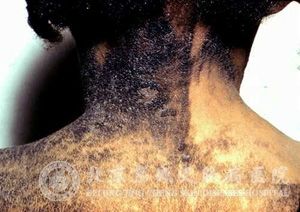

如何诊断表皮松解性角化过度鱼鳞病?鱼鳞病是一种比较常见的皮肤病,此病给我们的生活造成了很大的困扰,因为此病一旦病发便会波及全身,犹如鱼鳞一般,严重影响外观。很多患者由此产生自卑心态,严重影响了学习、工作和生活。只要正确的诊断表皮松解性角化过度鱼鳞病,并给以相应的治疗与护理便可以缓解鱼鳞病的症状,减轻患者的心理压力。

北京京城皮肤医院指出,表皮松解性角化过度鱼鳞病诊断要点:

1.出生时便有。

2.皮损在屈侧较重,特别在腋部、腹股沟区、腕肘等皱褶处更明显,甚至出现灰棕色疣状鳞屑。

3.全身覆盖盔甲样鳞屑,鳞屑脱落后出现粗糙潮湿的表皮,会有松弛性大疱,再度出现鳞屑,不断反复。

4.皮损遍及全身,呈限局性及线状等其他异型,如豪猪状鱼鳞病以疣状增殖和鳞屑为主的一种异型。

5.慢性病程,但病情随年龄增长会逐渐减轻。